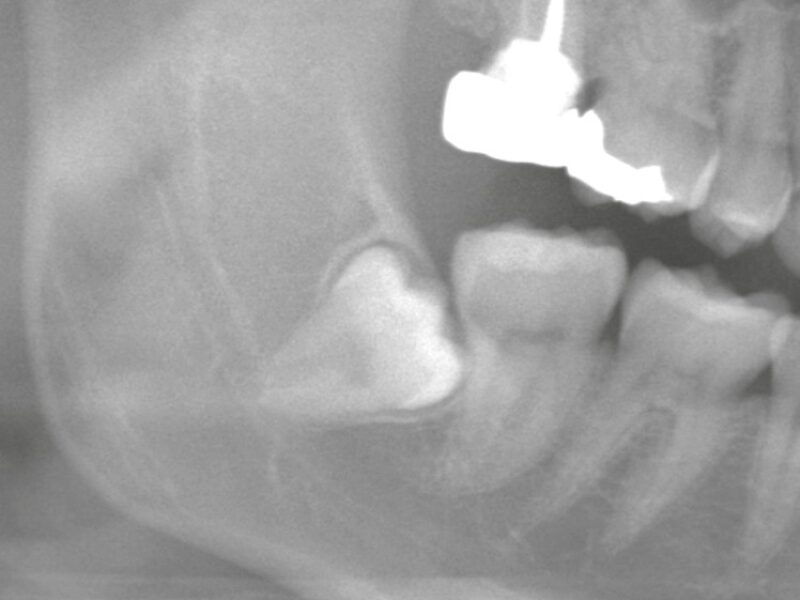

症例紹介

親知らずの抜歯や顎関節症の治療では、患者様の不安や症状にしっかり寄り添いながら、安心・安全な治療を提供しています。

「難しいと言われた親知らず」「顎の不調が治らない」などのお悩みは、ぜひ一度、当院へご相談ください。